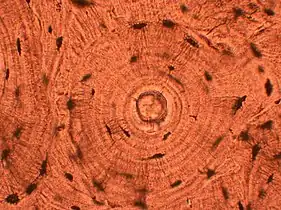

- Cartwheel pattern: Center points that radiate cells or connective tissue outward